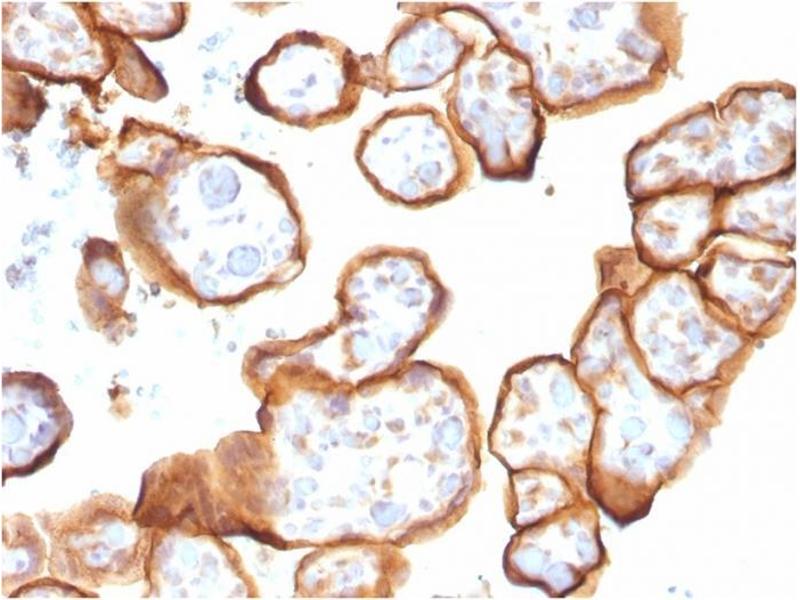

THBD 适用: 人 IHC, ELISA, Coat, ISt, StM 宿主: 小鼠 Monoclonal rTHBD-1591 unconjugated Recombinant Antibody

产品编号 ABIN6940729

100 μg (More quantities available)

发货至: 中国

获取报价